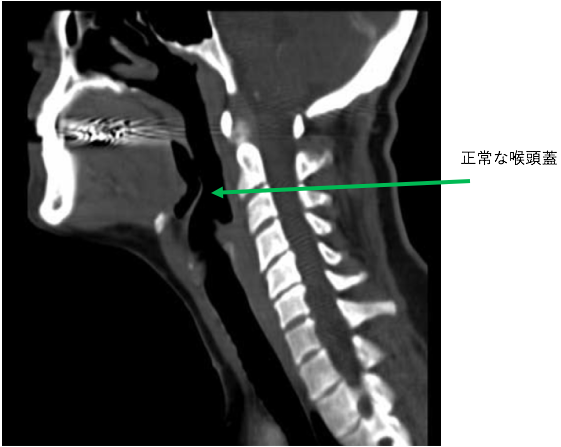

喉頭蓋は舌の付け根にあります。大部分が軟骨で構成されています。飲食時に食べ物や液体が気管に入るのを防ぐ弁の役割を果たします。